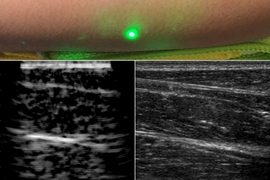

In 2019, the team demonstrated that the NCLUS proof-of-concept (GEN-1) system can acquire ultrasound imagery from human subjects using skin-safe lasers — a first in the medical community. However, the time to acquire the image data from the patient subject was long and impractical for clinical practice. In addition, the GEN-1 system image resolution was significantly less than that of state-of-the-art medical ultrasound.

Significant engineering development has since occurred to transition NCLUS GEN-1 to an operational system appropriate for clinical testing. In the clinical NCLUS system, both the laser source and receiver are miniaturized and housed inside an optical head attached to a portable armature. The lasers that pulse and scan are 500 times faster than those of the GEN-1 system, thus reducing the entire image-data acquisition time to less than a minute. Future NCLUS prototypes will involve faster acquisition times of less than one second. The new clinical system also operates at much higher ultrasound frequencies than those of the GEN-1 system, enabling resolution down to 200 microns, which is comparable to the resolution of state-of-the-art medical ultrasound.

The moveable armature enables many degrees of freedom to view the various regions of the body. Inside the optical head are also programmable fast-steering mirrors that automatically position the source and receive laser beams to precisely establish the ultrasound array. A 2D lidar is used to map the patient's skin surface topography; a high-frame-rate short-wave-infrared camera records the laser source and receiver projected locations on the skin, providing the array parameters necessary for constructing ultrasound images. The skin-surface topography mapping and laser-position recordings are registered by using natural skin features such as freckles. In this way, a fixed reference frame is established for performing precise repeat scans over time.

The NCLUS clinical system generates fully automated and registered ultrasound images via synthetic aperture processing. The team demonstrated this system on a gel-based puck synthesized to match the mechanical properties of human tissue (referred to as a phantom) that control ultrasound wave propagation.